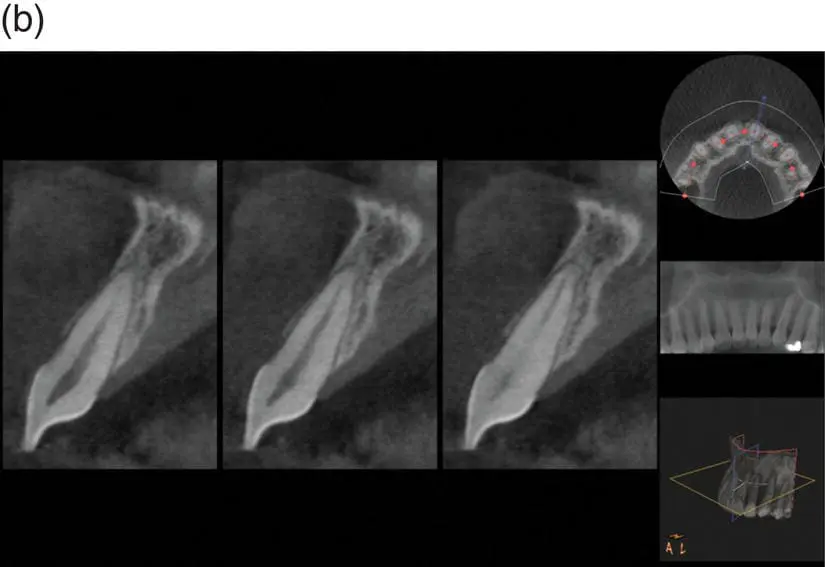

Todos sabemos que é comum a Reabsorção Radicular Induzida pelo Tratamento Ortodôntico (RRITO). Vários estudos têm relacionado a quantidade de reabsorção radicular à diversas causas possíveis. Seriam exemplos a duração do tratamento, o tipo de aparelho e a força aplicada. Mesmo que tenham trazido informações úteis, a maioria tem usado radiografias 2D. Recentemente, as imagens da tomografia computadorizada de feixe cônico (TCFC) têm possibilitado a realização de medidas mais acuradas da RRITO. Assim, os autores fizeram esse novo estudo para responder a seguinte pergunta:

“Qual é a quantidade média de RRITO medida em imagens de TCFC?”

Desfecho: A quantidade de reabsorção radicular medida em imagem de TCFC.

Em resumo, eu acho que podemos concluir, com certa cautela, que quando a TCFC é utilizada para medir RRITO, a quantidade média de reabsorção é entre 0,6 e 0,8mm. Isso é baixo e reconfortante.

Evaluation of orthodontically induced external root resorption following orthodontic treatment using cone beam computed tomography (CBCT): a systematic review and meta-analysis.